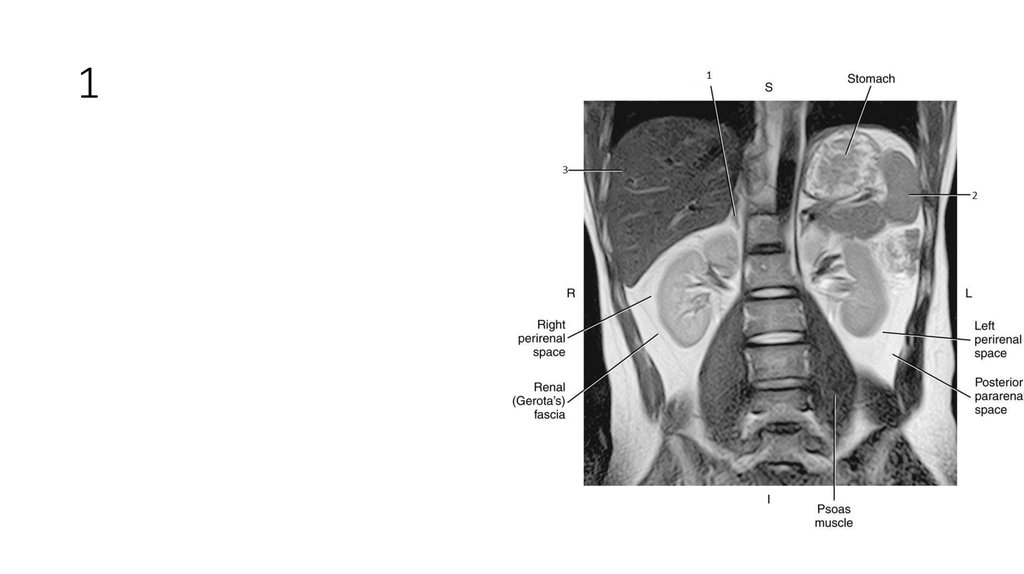

2. 1

3. 1

• Liver

4. 2

5. 2

• Spleen

6. 3

7. 3

• Aorta

8. 4

9. 4

• Inferior Vena Cava (IVC)